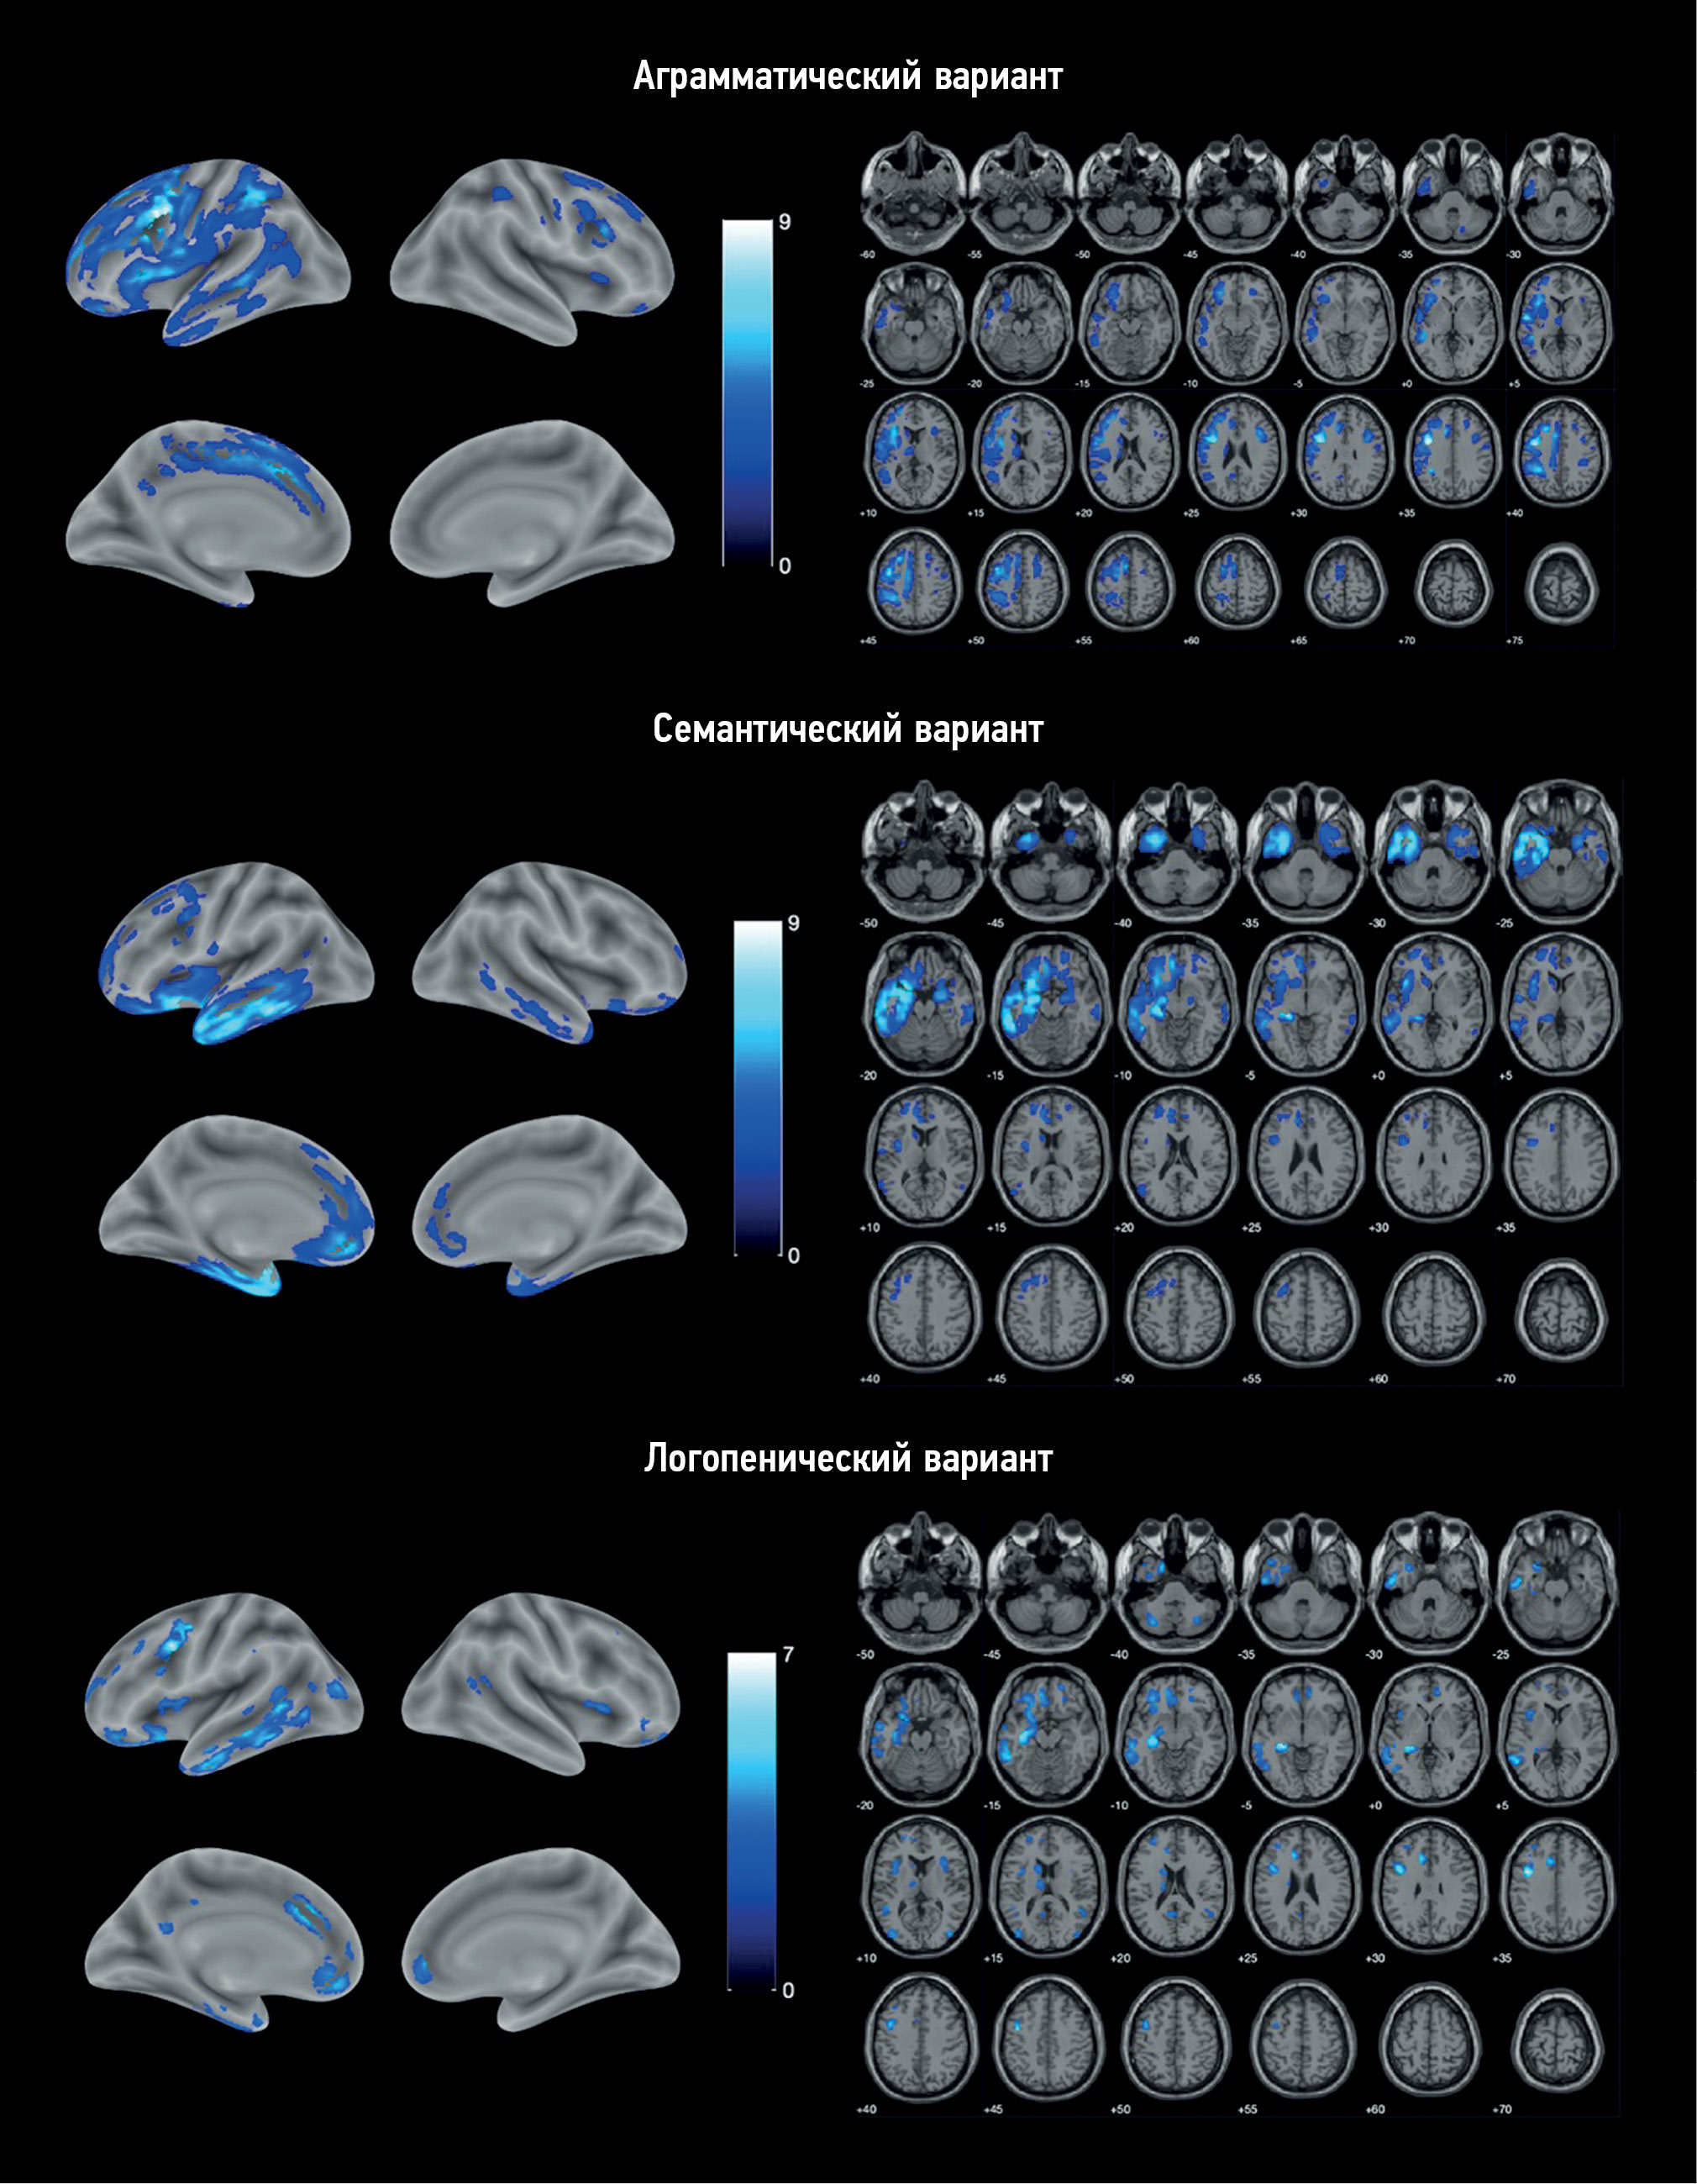

Left ventricular noncompaction with ventricular aneurysm in a 6-year-old patient

Ventricular noncompaction is a rare type of cardiomyopathy often associated with a ventricular aneurysm. We present a clinical case of a 6-year-old female who arrived at our clinic complaining of physical exertion. Echocardiography revealed prominent trabeculations in the left ventricular wall and a lateral-basal part bulging out, indicating noncompaction of the left ventricular myocardium with an aneurysm. With a noncompacted-to-compacted myocardium ratio of 2.6, magnetic resonance imaging revealed the presence of noncompacted myocardium. It also revealed impaired left ventricular systolic function and a left ventricular aneurysm with myocardial scarring. Coronary angiography ruled out coronary artery disease. Therefore, myocardial scarring was caused by noncompacted myocardium microcirculatory disorder.

625-632